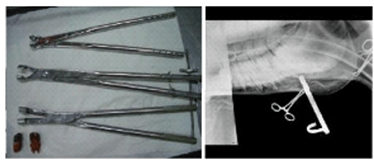

Traditionally teeth were extracted by making a hole in the face (for an upper tooth) or the jaw (for a lower tooth) and hammering out the tooth. Now it is much more common to extract teeth from the mouth by using large dental extractors (below) to loosen a diseased tooth and pull it free.

Oral extractions require substantial patience as it can take 6-8 hours to wiggle the tooth loose. Great care must be taken not to fracture the tooth or leave fragments behind. The teeth at the bottom left of the picture above are from a 20-year-old horse and only a third of the length of those in 7 year-old.

Occasionally, and especially in young horses, it is not possible to extract a tooth orally. In these cases, the horse is anaesthetised and a dental punch inserted through a hole made in the jaw bone or face to hammer out the tooth. The picture on the right above shows an Xray taken during surgery to check that the dental punch is correctly positioned prior to being hammered.